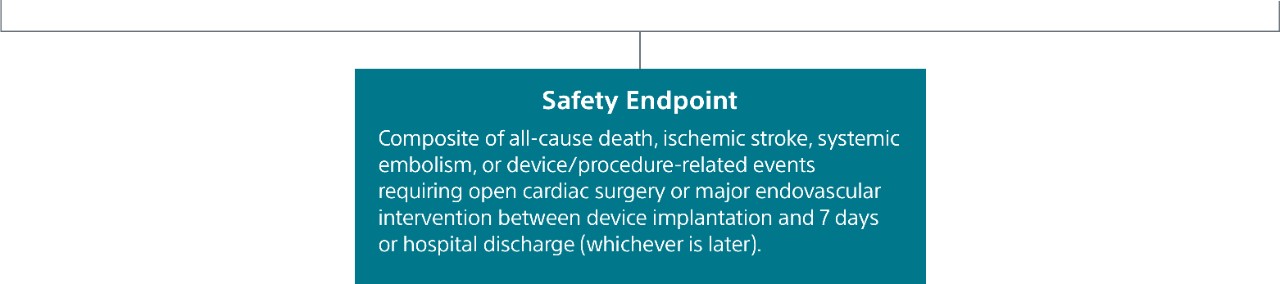

SURPASS demonstrated 0.37% major procedural adverse event rate within 7 days or hospital discharge in 16,048 commercial patients and confirmed the trusted safety profile of WATCHMAN FLX in real-world clinical practice setting.

The SURPASS Data reinforces the excellent safety profile WATCHMAN FLX demonstrated in the PINNACLE FLX Trial, with the largest (n=16,048) real-world WATCHMAN FLX patients studied to date.

Surpass 1 Year Results

Study Design

- The objective of this SURPASS analysis is to assess long term safety and efficacy outcomes at one year with WATCHMAN FLX in a routine, real-world setting.

- This analysis includes the largest commercial WATCHMAN FLX patient population to date, with 66,894 patients implanted between August 5, 2020 and March 31, 2022.

Patient Characteristics:

- Age: 76.2 ±7.9 Years

- CHA2DS2-VASc Score: 4.8±1.5

- HAS-BLED Score: 2.4±1.0

- Women: 41%

- Clinically Relevant Bleeding: 57.7%